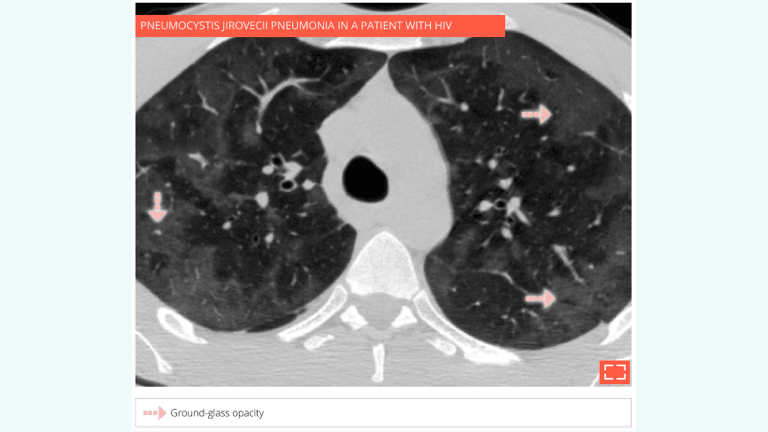

•  Slightly increased attenuation of lung parenchyma, with preservation of vascular and bronchial margins.

• Pulmonary infection: pneumocystis jirovecii pneumonia, cytomegalovirus (CMV), etc.

• Heterogeneous distribution of ground-glass opacity giving the appearance of a mosaic pattern.

• Note that the size of pulmonary blood vessels is identical in hypo- and hyperdense regions, suggesting alveolitis.